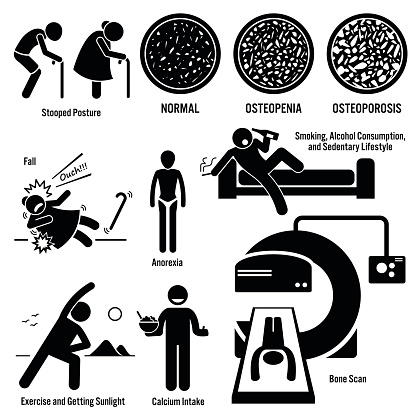

Every year, at least 250,000 people are hospitalized for hip fractures, yet many don’t realize the injury is associated with osteoporosis risk. New research suggests that seven out of 10 older adults who experience hip fractures are not told they could have osteoporosis. Osteoporosis is a condition in which the bones become brittle and fragile ...click here to read more